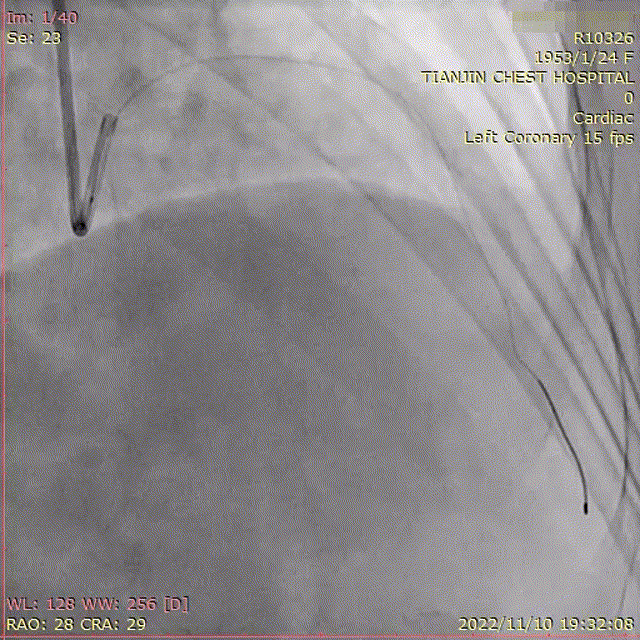

左冠多体位造影

冠脉造影:右冠未见明显狭窄,LAD中段管状狭窄90%。